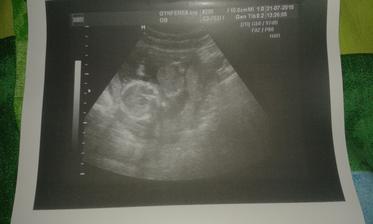

@lenkato7 áno od 20. 5. keď bilo srdiečko to je potvrdené a radujem sa najviac na svete 🙂 ďakujem a dúfam že sa čoskoro pridáš ♥

@anonymmb jeeej zlatá si ♥ áno 6. 1. mám termín 🙂 a prišlo to presne vtedy keď sme najmenej čakali 🙂